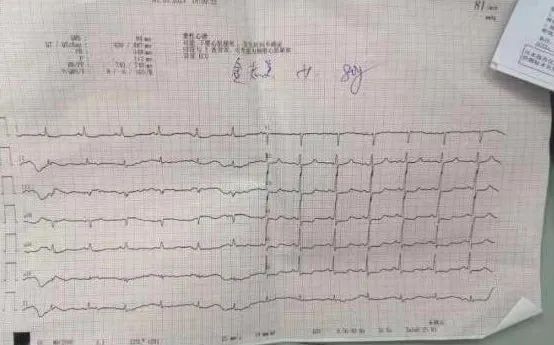

患者急诊心电图提示avR导联ST段抬高0.05mV,I、avL、V3-V6导联ST段压低0.05-0.1mV,心肌酶谱超敏肌钙蛋白T明显升高(大于正常范围上限3倍以上)。